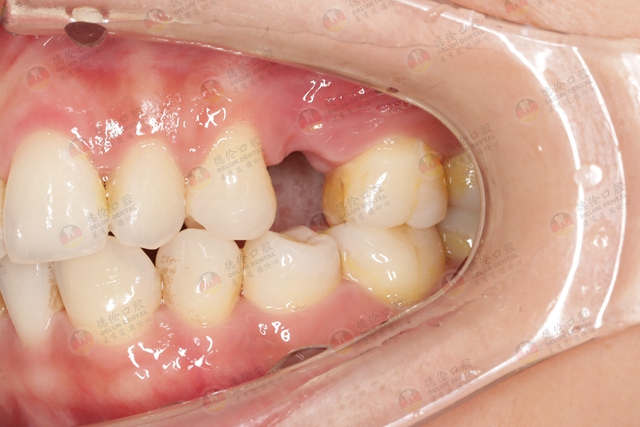

牙齿缺损不仅是影响形象美观、饮食等问题,对整个人的身体健康也有很大的影响。尤其是牙齿缺失,如果置之不理,还会影响整副牙齿。

牙齿缺损和牙齿缺失的区别

牙齿缺损和牙齿缺失是不同类型的牙齿问题。

牙齿缺损是指牙齿表面的损伤、裂缝或磨耗,它可能是由于牙齿磨损、牙齿龋齿、外力撞击等原因导致。

牙齿缺损可能仅会导致牙齿变丑、感觉敏感等一些轻微的问题,通常可以通过补牙、烤瓷牙等治疗方法来修复。

而牙齿缺失是指牙齿从牙槽骨内完全脱落或其他原因导致牙齿整体缺失,它可能是由于脱落、受伤、疾病、佩戴义齿等多种原因导致。

牙齿缺失无法通过简单的修复来解决,需要进行更为复杂的牙齿植入手术或者其他义齿修复治疗方式来解决。

01、牙齿缺损修复治疗方式

牙齿缺损的修复方式取决于牙齿缺损的程度。